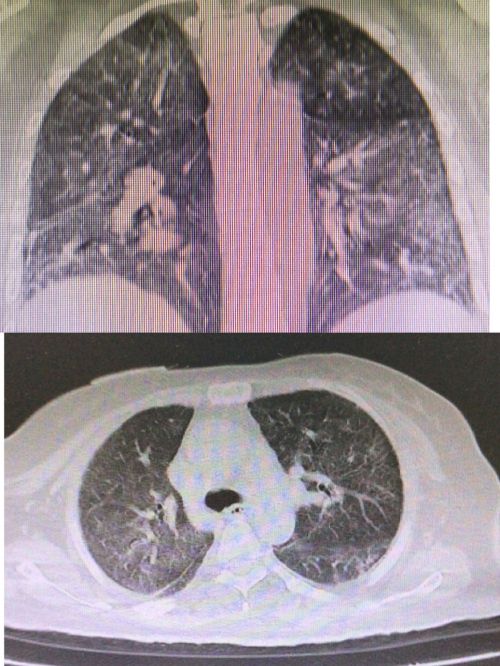

患者入院时肺部影像可见大片“白肺”。

复查肺部ct显示:肺部病变较前明显吸收改善。